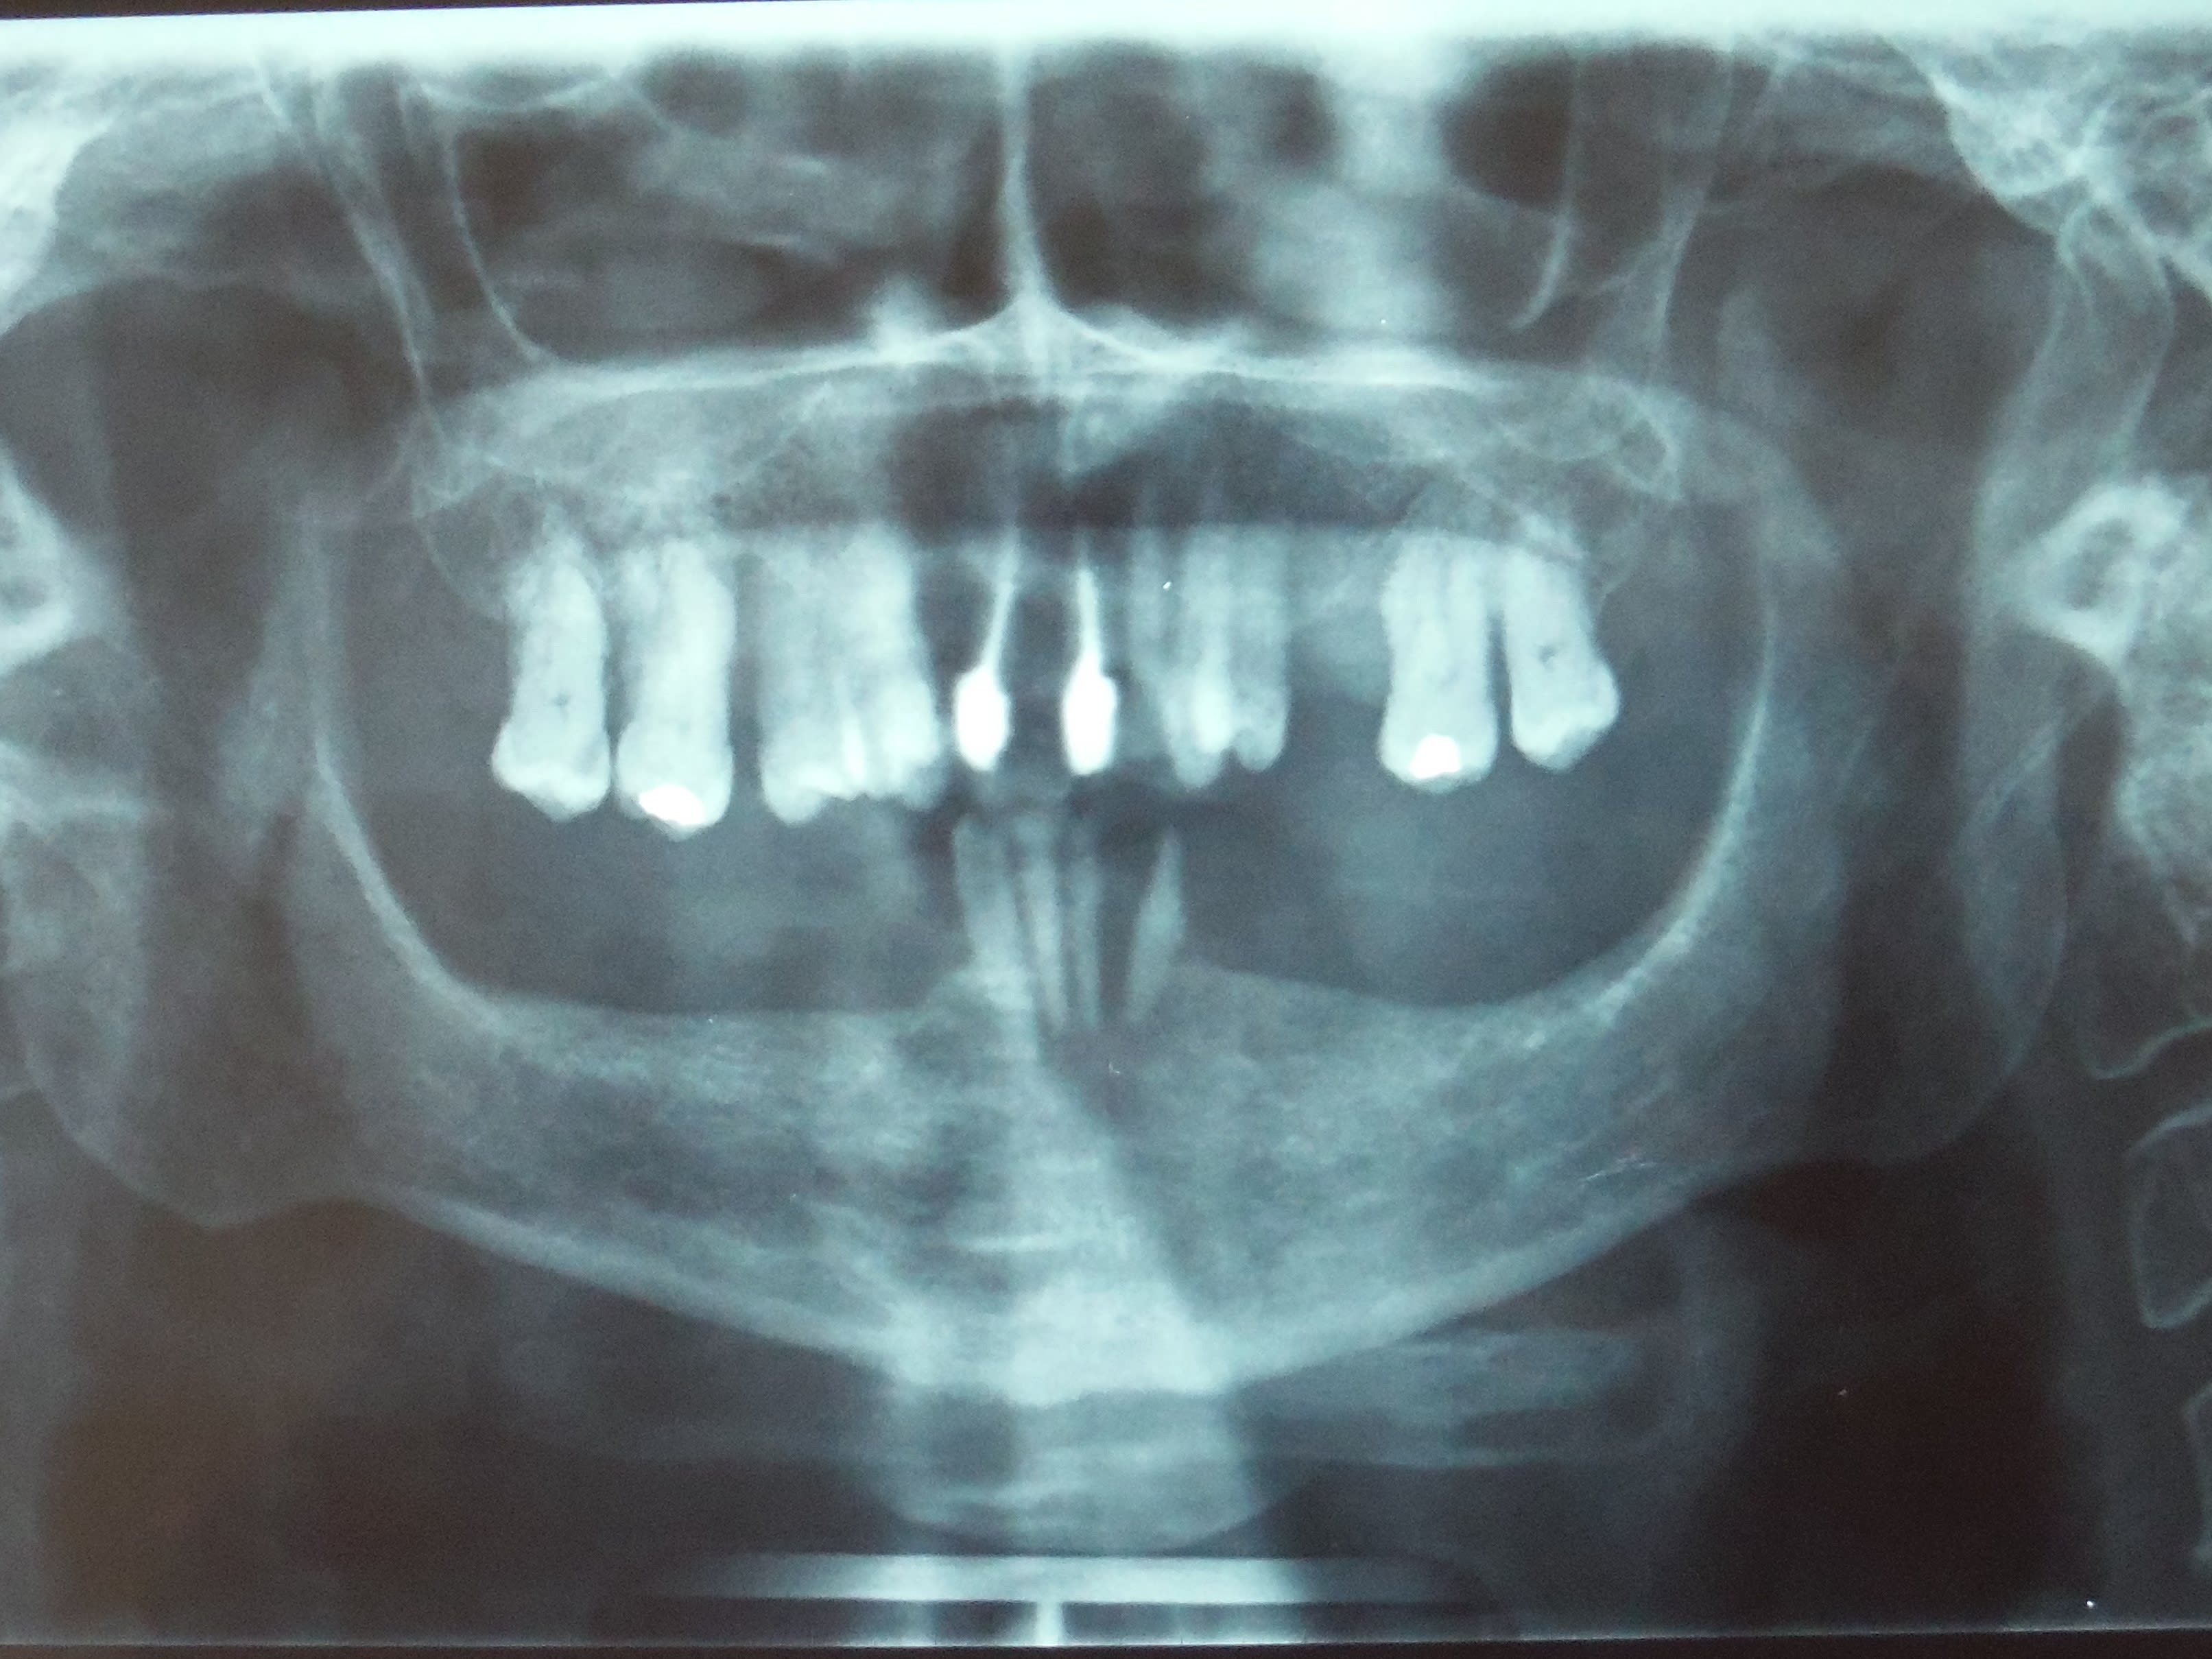

22/12/2016 à 21h10

pano ci-jointe

patiente avec peu de moyens financiers.